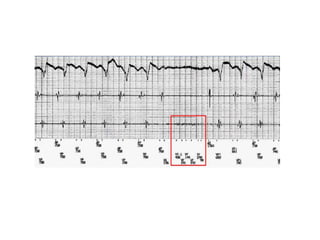

Beat-to-beat auto-adjusting sensitivity

Sinus rhythm – To avoid oversensing T waves

VF – To avoid undersensing